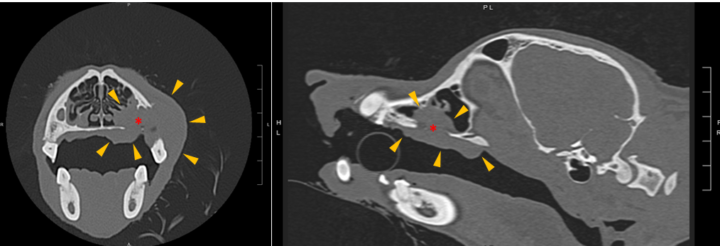

Imaging of the head should be performed via radiography or, ideally, computed tomography (CT) to assess the extent of local disease (Figure 2). Computed tomography is significantly more sensitive at detecting bone lysis and adjacent tissue invasion compared to radiographs, both of which are important factors for surgical planning (Ghirelli et al., 2013).